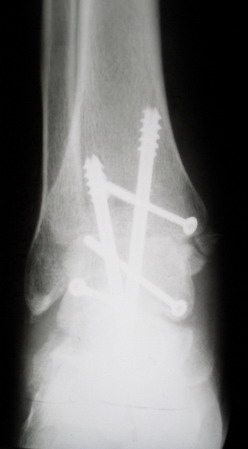

Ваша дискуссия заставила перелистать свои наблюдения.

Среди повреждений таранной кости (Hawkins III-IV) с одновременной травмой лодыжек встретилось следующее (см. вложение). Пациент упал в колодец на глубину 10 метров (Х.2002 г.), госпитализирован с диагнозом: з/перелом шейки правой таранной кости (Hawkins IV) с переломовывихом тела назад и кнутри, закрытый перелом внутренней лодыжки и переднего края большеберцовой кости. Оперирован в первые 12 часов после травмы, выполнена открытая репозиция таранной кости, внутренним и передне-внутренними доступами, остеосинтез переломов шейки и тела губчатыми винтами, для реваскуляризации тела таранной кости первичный компрессионный над- и подтаранный артродез. Синтез внутренней лодыжки губчатым винтом. Удаление винтов через 1 год,2 мес. Получен анкилоз указанных суставов с сохранением длины конечности, полная реваскуляризация таранной кости, о чем говорит сращение ее переломов, отсутствие отеков и

цианоза стопы и голени. Компенсаторная подвижность переднего и среднего отделов стопы около 15-20 градусов за счет поперечного (Шопара) сустава стопы. Считаю оправданной подобную тактику, не смотря на угрожаемый прогноз (100% асептический некроз) по классифицкации Hawkins.